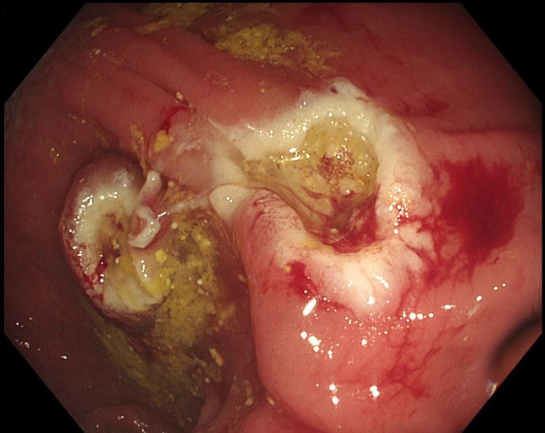

Ergebnisse: In der Akutdiagnostik zeigte sich sonographisch eine Harntransportstörung III° bds., laborchemisch ein akutes Nierenversagen mit einem Kreatinin von 2,3 mg/dl sowie eine beginnende Infektkonstellation (Leukozyten von 12,95 Tsd/µl, CRP von 3,7 mg/dl). Das im Anschluss durchgeführte CT zeigte eine Hydronephrose beidseits sowie ektatische Ureteren bis zur Insertionsstelle im Sigma, wobei die Clips in unmittelbarer Nachbarschaft lokalisiert schienen. Es erfolgte die Anlage von Nierenfistel-Kathetern (NFK) bds. sowie die koloskopische Entfernung der Clips. Laborchemisch normalisierten sich die Retentionsparameter. Nach 3 Wochen objektivierte eine antegrade Darstellung über die NFKs rechts einen regelrechten Abfluss, während sich links ein Kontrastmittelabbruch im Bereich der Einmündung des Ureters in das Sigma zeigte. Somit verblieb der NFK links als Dauerversorgung. Aufgrund des Patientenalters entschieden wir uns gegen eine Neueinpflanzung oder anderweitige Harnableitung.

Schlussfolgerung: Das Vorliegen einer US ist ein seltener Situs im klinischen Alltag. Daraus ergibt sich, dass diese Rekonstruktionstechnik in anderen Disziplinen oftmals nicht mehr ausreichend Beachtung findet. Da die Harnleitermündungen als polypoide Veränderungen im Rahmen endoskopischer Interventionen missinterpretiert werden können, entstehen zusätzliche Risiken. In diesem Fall hat dies zu einem iatrogenen Verschluss der Harnleitermündungen und im weiteren Verlauf zu einer Dauerableitung der linken Niere mittels NFK geführt. Bei erhöhtem Risiko für kolorektale Polypen und malignen Veränderungen im Bereich der Anastomose nach US ist eine Abtragung nur bei hochgradig malignitätsverdächtigen Läsionen sowie einer interdisziplinären Zusammenarbeit sinnvoll, um o.g. Komplikationen zu vermeiden.

Abbildung 2 [Abb. 2]